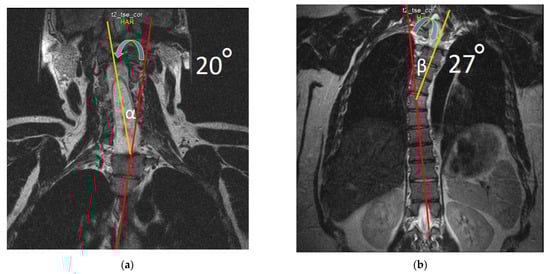

2.4. Neuroimaging